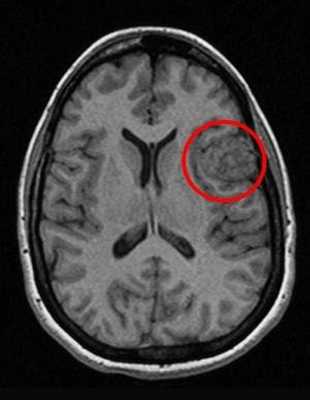

Как же узнать, есть ли на снимках признаки болезни? Самое главное - запомнить, как выглядит головной мозг здорового человека. Врач, изучая снимки пациентов, постоянно сравнивает их с нормальными снимками, хранящимися у него в голове. Чтобы понять, как это происходит - посмотрите на снимки внизу:

Перед вами - два снимка, сделанных в одном режиме. Снимок снизу - норма. Какое заболевание, в таком случае, есть на верхнем снимке? Чтобы понять это, нужно сравнить эти изображения. Явно видно отличие - на верхнем снимке в правой части головного мозга есть новообразование. Разница еще заметнее, если сравнить левую и правую части того же снимка.

Отметим его красной окружностью. Визуально оно представляет собой узел, неоднородный по окраске и отличающийся от серого и белого вещества головного мозга. В таких случаях, чтобы точно определить границы опухоли и определить её тип исследование повторяют с контрастом. Введение контрастного препарата в кровь через локтевую вену приводит к накоплению контрастного вещества в тканях опухоли - нормальные здоровые ткани его практически не накапливают. И мы получаем следующую картину, показанную на рисунке справа. Яркая окраска опухоли соответствует накопленному контрасту - теперь можно не только сказать, где опухоль, но и примерно определить, что это доброкачественная опухоль, так как она имеет четкие границы (злокачественные опухоли прорастают окружающие ткани, из-за чего границы будут размытыми и не такими четкими).